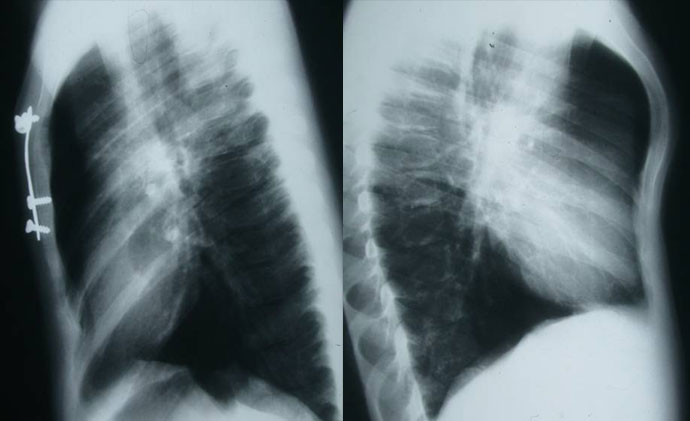

En los tipos condrogladiolares se puede llevar a cabo una técnica minimamente invasiva descrita por Abramson similar a la desarrollada por Nuss pero a la inversa. Se coloca una férula metálica subcutánea que reduce la protusión y se fija con unos estabilizadores laterales a la pared torácica.